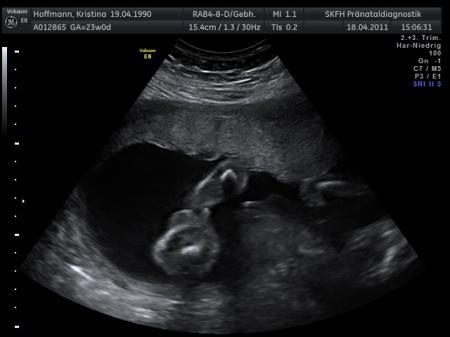

So ich hab hier mal die beiden Ultraschallbilder, Ansicht sozusagen von unten auf den Popo, (ach ich war so Stolz, mein Würmchen lag sooo Perfekt!) Und da der FA ja nichts dazu sagen wollte ausser "Wenn sie was sehen wirds ein Junge, wenn nicht ein Mädchen", seid Ihr nun gefragt: Was könnt Ihr hier erkennen? Wirds ein Mädchen oder ein Junge? Ist da was oder nicht? Und warum kann ein Ultraschallbild nicht einfach deutlicher sein? ich weiß es einfach nicht... Liebe Grüße Phenolein

Bild zu Raten wir gemeinsam - Forum für August - Mamis

Also ich würde meinen Schamlippen dort zu sehen!!!! ich denke es ist ein Mädchen!!!! Die Schamlippen sehe ich da wo die feinen weißen Striche sind!! Lg

Auf dem ersten Bild ist Links ein kleines weißes Kreuz, direkt da drüber solls wohl sein, wie gesagt ich erkenn darauf auch net viel :D Ich weiß aber auch nicht wie zum Vergleich ein Jungen-Ultraschall aus dieser Perspektive Aussehen soll... Aber ich hab auch die Vermutung da kein Schniedelchen drauf zu sehen

Stell das Foto doch ins Expertenforum, Herr Bluni erkennt bestimmt was;) Ich wird sagen Mädchen drei Striche deutet auf Schamlippen aber sicher bin ich mir nicht. LG Dani